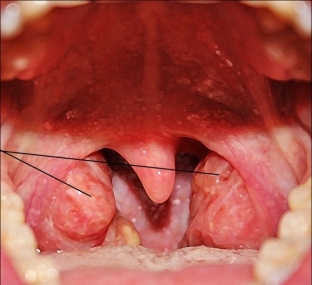

Аденоїди – це патологічно збільшені мигдалики в носоглотці. Носоглоточная мигдалина входить до складу лімфоїдного глоткового кільця Вальдера – Пирогова. Носоглоточная мигдалина добре розвинена в дітей віком, і з віком зменшується чи взагалі атрофується. До причин утворення аденоїдів відносять генетичну схильність до лімфатико-гіпопластичних аномалій конституції.

Виділяють 3 ступеня збільшення піднебінної мигдалики залежно від симптомів аденоїдів:

- 1 ступінь - аденоїди перекривають третину сошника і хоан. Вдень дитина дихає вільно, вночі в горизонтальному положенні носове дихання утруднене.

- 2 ступінь – аденоїди перекривають половину хоан та сошника у дитини. При цьому дитина завжди дихає ротом і часто хропе уві сні.

- 3 ступінь – аденоїди повністю або майже повністю перекривають хоани та сошник. Симптоми аденоїдів 2 ступеня виражені різкіше.